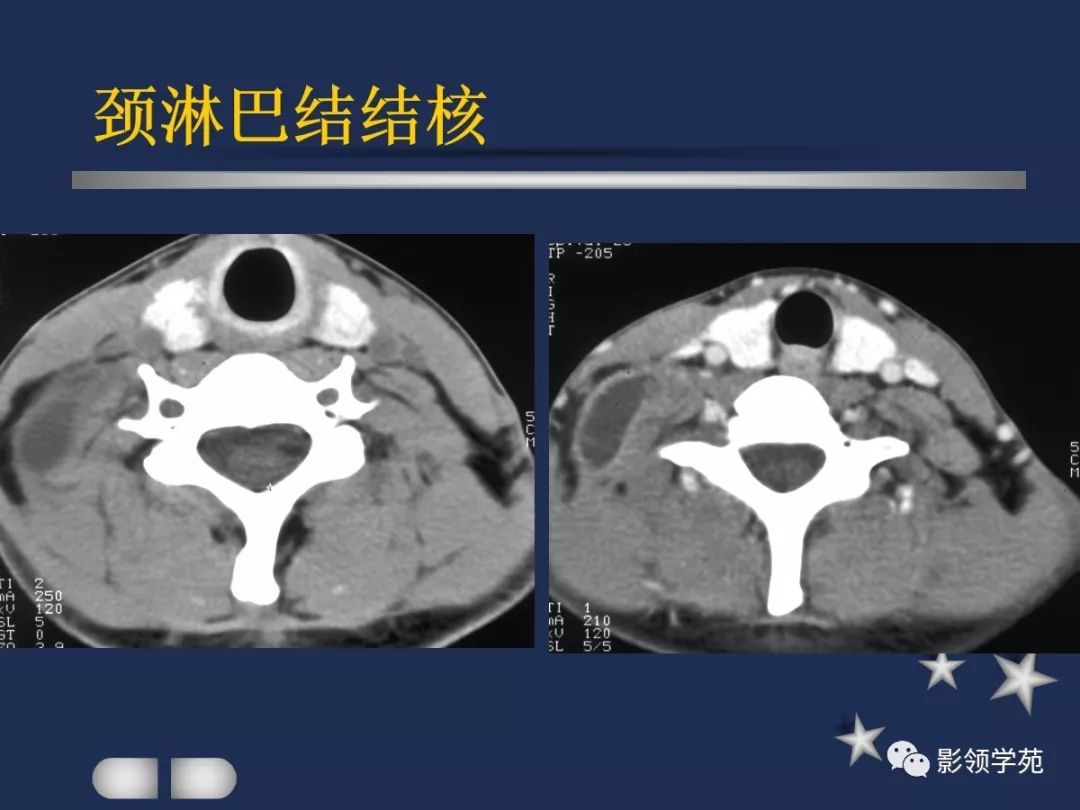

- 淋巴结肿大性疾病

- MRI上实性肿块在T1WI上呈等低信号,在T2WI上呈高信号,囊变区呈长T1长T2信号,钙化在T1WI及T2WI上均呈低信号。

- 在增扫时可见环状强化。

- 由于CT和MRI能增强扫描可以清晰显示甲癌的侵润范围和程度,以及显示淋巴结的转移情况